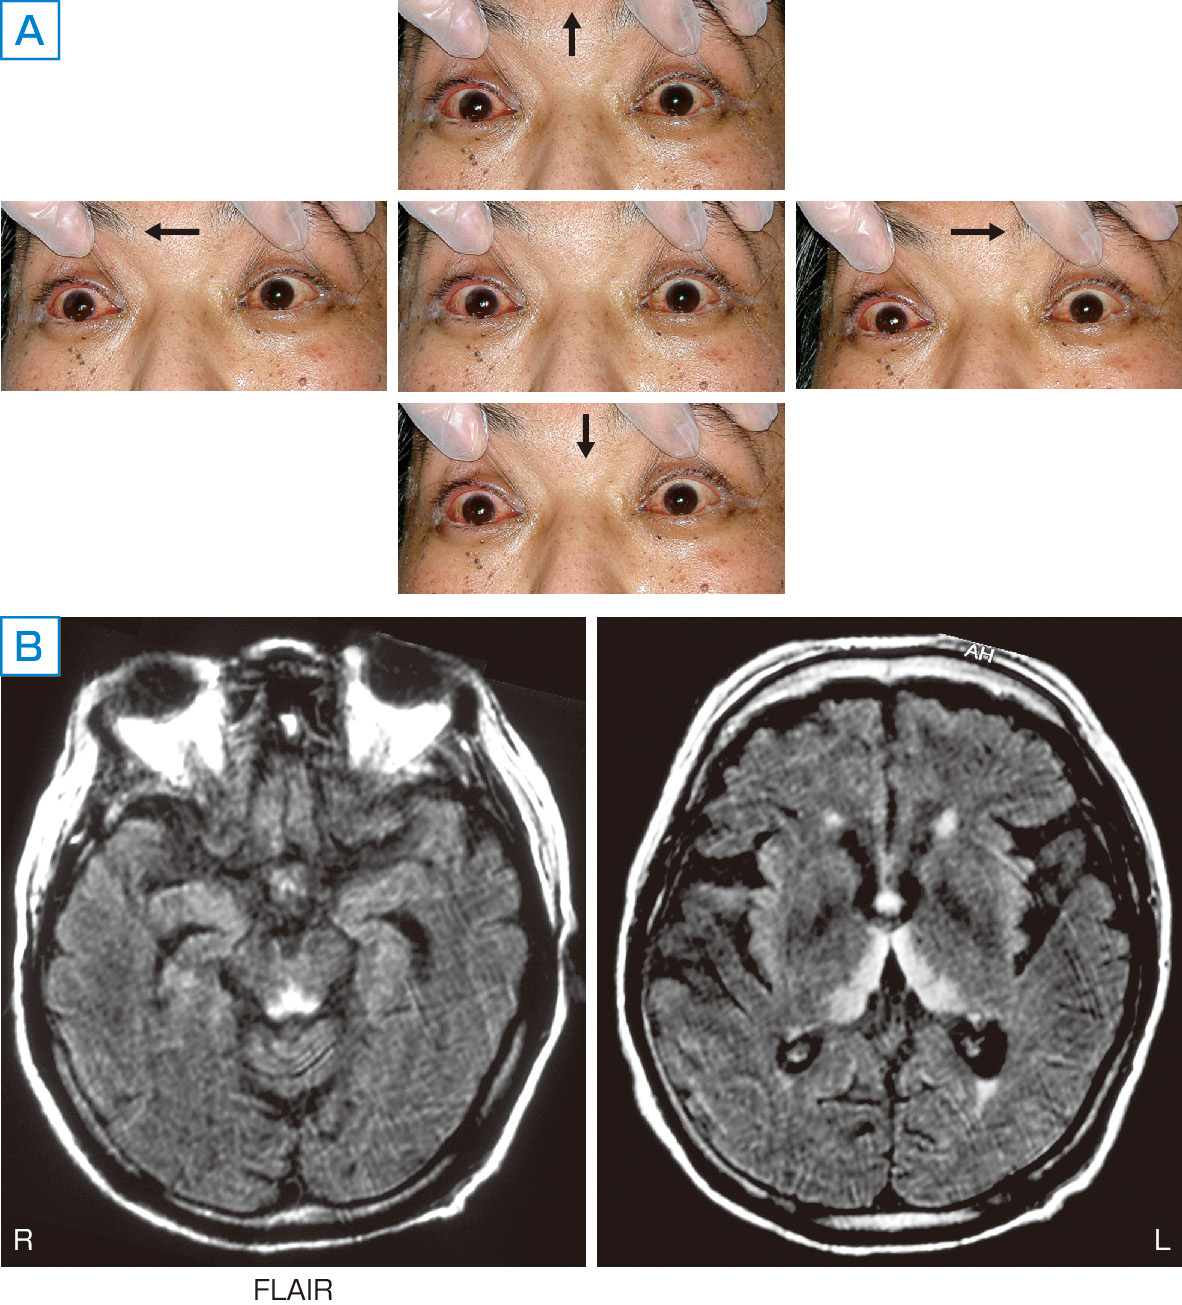

ⓔ図18-3-10 Wernicke脳症 下顎脱臼のため食事摂取が不十分となり,その後めまい感のため自宅で動けなくなり来院した55歳男性.血中チアミン濃度は5 ng/mL未満であった.眼球運動は全方向で制限され (A),MRIで特徴的な病変の広がり (中脳水道周囲,視床下部,乳頭体,視床内側部) が確認された (B).チアミン補充により症状,MRI所見とも完全に消失した.